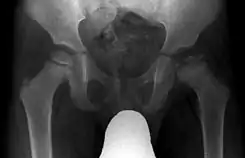

Imagen radiográfica anteroposterior de la cadera de un paciente con enfermedad de Legg-Calvé-Perthes